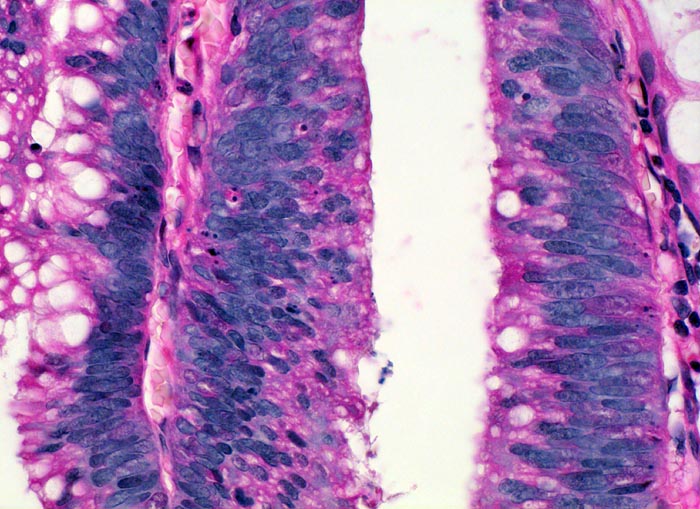

• Low grade Dysplasie (ca. 95%): Das Epithel der mässiggradig dysplastisch veränderten Drüsen zeigt vermehrte, vergrösserte, mehrreihig angeordnete stiftförmige Kerne mit leicht vergröbertem Chromatin und verminderter intrazytoplasmatische Schleimbildung. Die Zellpolarität ist erhalten (parallele Ausrichtung der Zellkerne zueinander, senkrecht zur Basalmembran).

• High grade Dysplasie (ca. 5%): Im Zentrum des Adenoms findet sich ein kleines Areal mit high grade Dysplasie: dysplastisch veränderter Drüsen mit kribriformer Architektur (Tubulus mit multiplen Lumina gesäumt von dysplastischen Zellen) und grösseren, abgerundeten Zellkernen teilweise in allen Epithellagen. Die Lumina der kribriformen Drüsen enthalten apoptotische Zelltrümmer und nekrotischen Detritus. Das sollte der Kliniker dem Pathologen mitteilen: